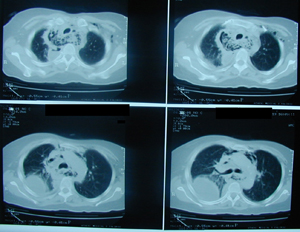

Εικόνα 2α-δ

Αξονική τομογραφία θώρακος σε διαφορετικά επίπεδα. Αναδεικνύει τα ίδια ευρήματα με την απλή ακτινογραφία και θέτει την διάγνωση της ρήξης της τραχηλικής μοίρας του οισοφάγου με εικόνα εμπυήματος του δεξιού ημιθωρακίου και εικόνα μεσοθωρακίτιδας με υδραερικό επίπεδο τόσο στο μεσοθωράκιο όσο και στον τράχηλο.